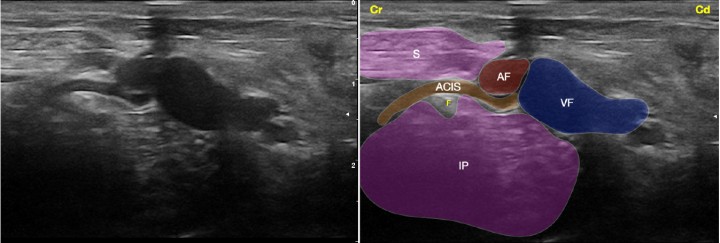

<p>Imagen ecográfica del nervio femoral a su paso por el canal femoral. Músculo sartorio (S), músculo iliopsoas (IP), arteria femoral (AF), arteria circunfleja ilíaca superficial (ACIS), vena femoral (VF), nervio femoral (F). Cr: Craneal, Cd: Caudal.</p>

Figura 2

Imagen ecográfica del nervio femoral a su paso por el canal femoral. Músculo sartorio (S), músculo iliopsoas (IP), arteria femoral (AF), arteria circunfleja ilíaca superficial (ACIS), vena femoral (VF), nervio femoral (F). Cr: Craneal, Cd: Caudal.

Bloqueo del nervio femoral/safeno con abordaje inguinal

Existen diferentes variaciones de esta técnica que aportan pequeñas modificaciones de la misma. Básicamente, se describe el posicionamiento del animal en decúbito lateral colocando la extremidad a bloquear en la posición superior. Se eleva la extremidad y se tracciona ligeramente hacia caudal. Se utiliza un transductor de alta frecuencia (9-15 MHz).

El transductor se coloca en la zona inguinal cortando transversalmente la arteria y vena femoral. Resulta aconsejable localizar la arteria ilíaca circunfleja superficial que emerge de la arteria femoral hacia craneal.[ García-Pereira FL, Boruta D, Tenebaum S, Paranjape V: Ultrasonographical identification of the superficial circumflex iliac artery as a landmark for location of the femoral nerve in dogs. Vet Anaesth Analg 2018; 45: 703-706. [PubMed] ] El nervio femoral se observa como una estructura nodular craneal a la arteria femoral ligeramente lateral a la arteria ilíaca circunfleja superficial. Se debe introducir la aguja en plano a través del vientre del músculo sartorio dirigiéndola hacia el nervio.[ Portela DA, Verdier N, Otero PE: Regional anesthetic techniques for the pelvic limb and abdominal wall in small animals: A review of the literature and technique description. Vet J 2018; 238: 27-40. [PubMed] , Campoy L, Bezuidenhout AJ, Gleed RD et al: Ultrasound-guided approach for axillary brachial plexus, femoral nerve, and sciatic nerve blocks in dogs. Vet Anaesth Analg 2010; 37: 144-153. [PubMed] , Echeverry DF, Gil F, Laredo F et al: Ultrasound-guided block of the sciatic and femoral nerves in dogs: A descriptive study. Vet J 2010; 186: 210-215. [PubMed] ] En este punto se administra el AL debiendo observarse su distribución alrededor del nervio (Fig. 7). Se recomienda la administración de 0,1 ml/kg de bupivacaína 0,5% o ropivacaína 0,5% con 0,5-1 µg/ml de dexmedetomidina. Al igual que se ha descrito para su localización suprainguinal, la visualización del nervio femoral a este nivel es complicada debido a una ecogenicidad parecida entre el nervio y las estructuras que lo rodean. El empleo del neuroestimulador permite confirmar su correcto posicionamiento antes de inyectar el AL observando la contracción del cuádriceps y la extensión de la rodilla. La administración del AL en este punto bloquea el área de inervación del femoral/safeno distal a la ingle, produciendo por tanto el bloqueo sensitivo del área de inervación del nervio safeno, junto con el bloqueo motor del músculo cuádriceps femoral inervado por las ramas motoras del nervio femoral.